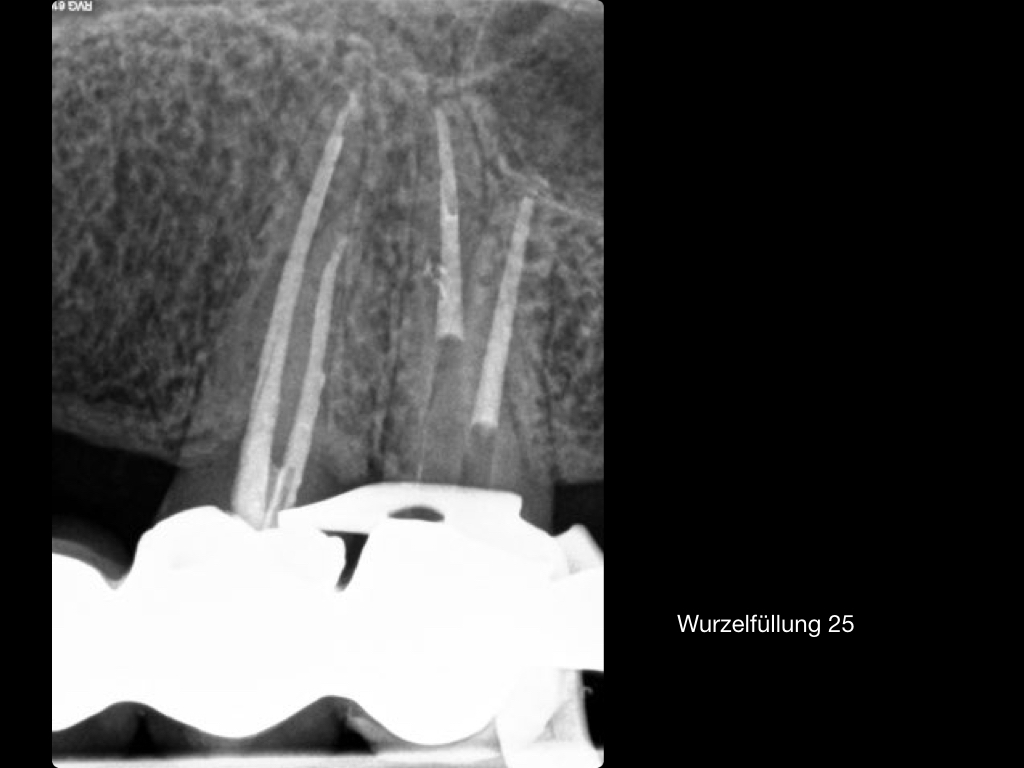

Es ist zu sehen … (2)